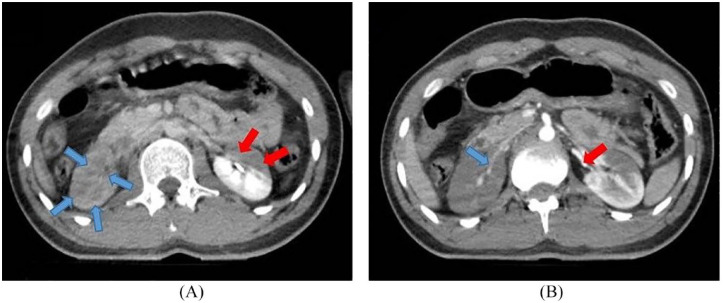

Case presentation: We report a case of 21-year-old man falling from a height of 9 m. A contrast-enhanced CT scan in the nephrogram phase showed no evidence of absorption in the right kidney and significantly decreased absorption in the left kidney. The pyelogram phase showed no secretion in the right kidney and decreased secretion in the left kidney suggesting segmental renal infarction. Subsequently, heparin infusion was initiated immediately. A follow-up contrast- enhanced abdominopelvic CT scan was performed after 1 month and showed no sign of infarction, and all laboratory tests were normal.